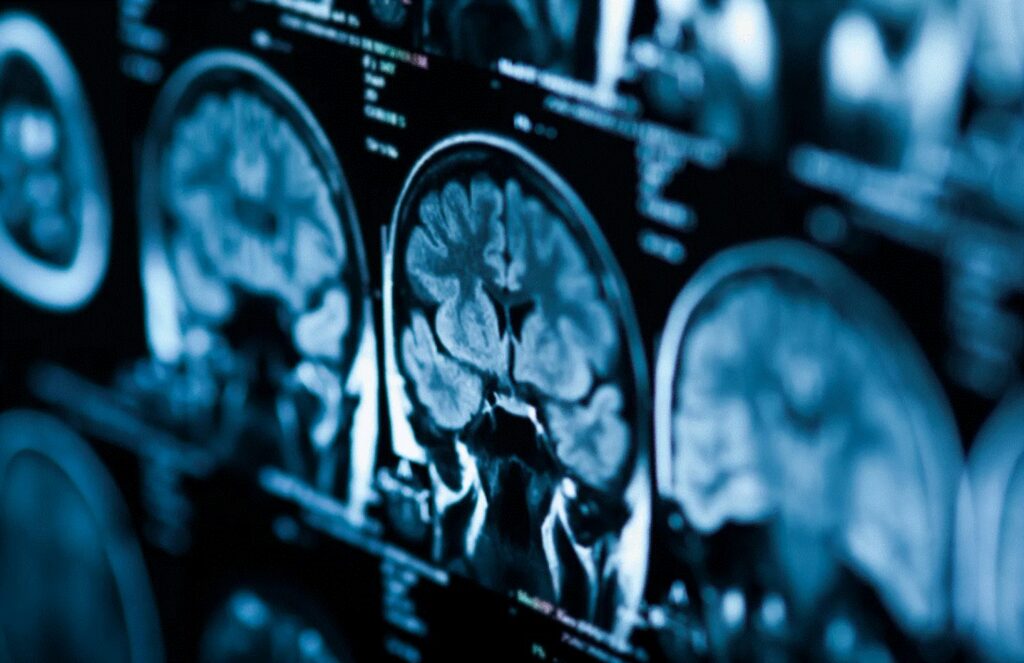

Studiul actual include predominant participanți albi; cercetătorii susțin necesitatea unor analize realizate pe populații mai diverse din punct de vedere etnic și geografic pentru a confirma universalitatea acestor modele. Cercetarea a fost realizată de o echipă condusă de Alexa Mousley (Universitatea din Cambridge), pe baza analizei a aproximativ 3.800 de scanări RMN provenite din mai multe baze de date din Marea Britanie și Statele Unite, inclusiv proiecte mari de imagistică cerebrală care au exclus persoane cu afecțiuni neurologice sau psihiatrice. Rezultatele au fost prezentate și analizate în presa științifică internațională și se aliniază cu date mai vechi despre îmbătrânirea accelerată a organismului uman.